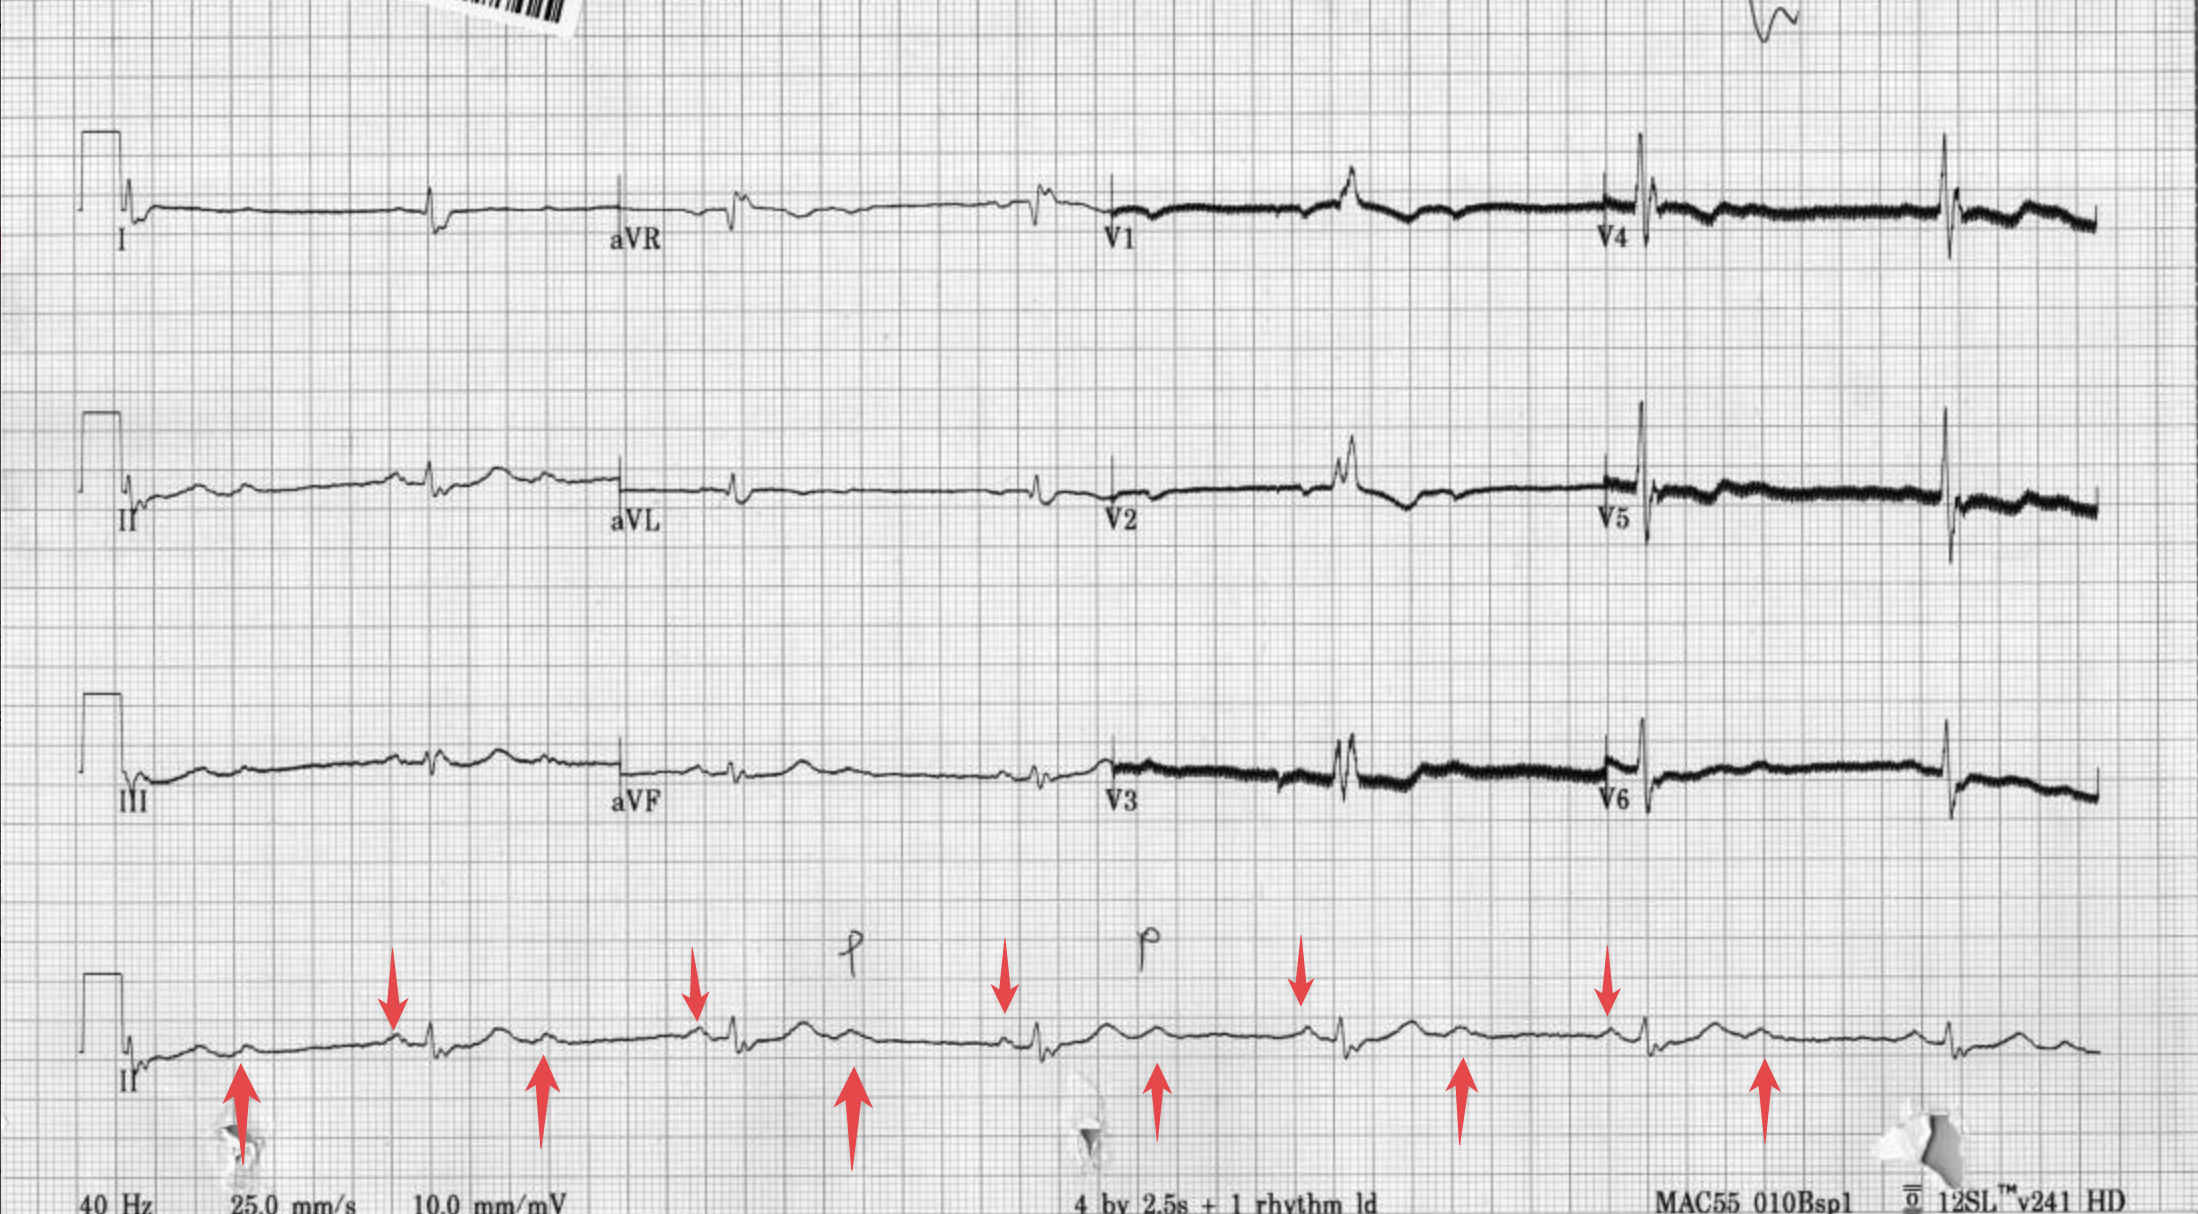

這位67歲的病患到院時的ECG如下:

Rate: 42 bpm

Rhythm: SR,但是出現多個P wave➔可以見到T wave後面又多一個P wave,這個P後面沒有立馬接個QRS,代表atrium放電往下傳,傳不到ventricle就斷電了

- PP interval都是regular、這是一張典型的2:1 AVB

Axis: normal axis

Interval: No QT prolong

Ischemia: RBBB pattern,但是沒有看到任何ST deviation

但是這邊的J point似乎在isoelectric baseline,要小心。

此病患ER arrival的ECG是RBBB pattern,且有rsR',照理說應該要看到STD,但是J point位於isoelectric baseline。

所以Keep in mind,如果這病患真有ACS S/S,必須把OMI列入DDx裡面。

我把ER arrival的ECG其long lead II拉出來看。

這是2:1 AVB,既不能稱Mobitz type 1,也不能稱Mobitz type 2。因為T wave後面接的P wave,沒有再接一個QRS,所以不知道P和QRS之間的關係是越拉越遠、還是固定PR interval之後的一個P wave後沒接QRS